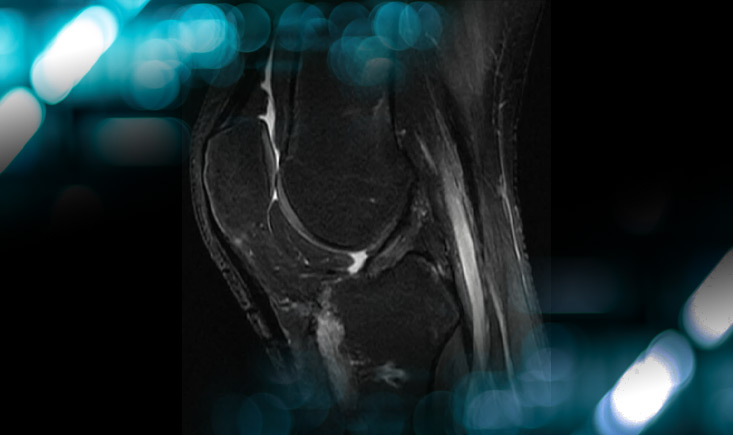

Pre operative MRI

- Knee X-ray: No fractures or bony avulsion

- Knee MRI Findings:

- Rupture of the PCL, PLC and LCL

- Intact ACL

- No meniscal tear

- No cartilage injury